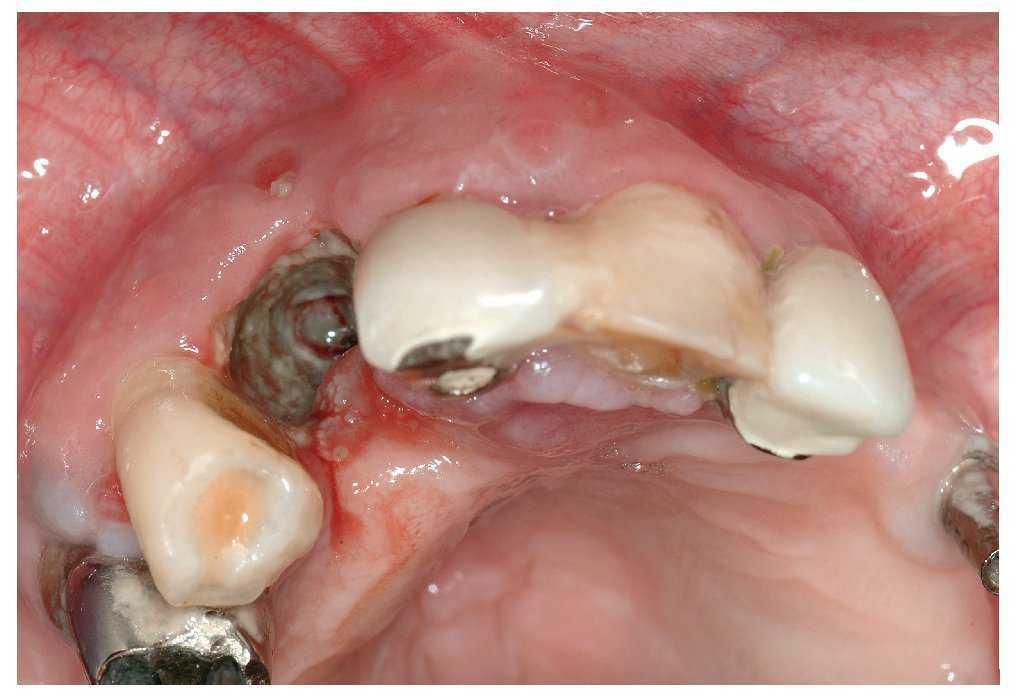

El signo clínico característico de la osteonecrosis asociada a bifosfonatos es un hueso de color blanco amarillento expuesto en el maxilar y/o en la mandíbula. El sondaje del hueso expuesto no suele provocar hemorragias y, por regla general, el paciente está asintomático22. No obstante, en áreas óseas extensas denudadas se pueden producir infecciones secundarias con un cuadro que incluye inflamación, producción de pus y dolor17. En pacientes dentados, la osteonecrosis imita a veces inicialmente un cuadro de periodontitis marginal. Después de la extracción, la cicatrización evoluciona de forma tórpida acompañada de una exposición ósea progresiva (figs. 1a a 1c). Una región afectada frecuentemente en la primera fase de la osteonecrosis asociada a bifosfonatos es la cortical lingual de la región de los terceros molares inferiores (figs. 2a y 2b). En los pacientes edéntulos se afectan a menudo zonas de la cresta alveolar maxilar y/o mandibular expuestas a la presión masticatoria directa de las prótesis totales (figs. 3a a 3c, 4a y 4b).

Figura 3a. Radiografía panorámica de una paciente de 68 años con un carcinoma de mama con metástasis óseas. Desde el año 2002 la paciente es tratada periódicamente con bifosfonatos intravenosos (Aredia). En 2006, el odontólogo de la paciente extrajo parte de los dientes de la mandíbula y la totalidad de los dientes superiores. La curación evolucionó de forma tórpida, sobre todo en la mandíbula, y provocó precozmente una dehiscencia de tejidos blandos. Así y todo, esta paciente no nos fue remitida hasta al cabo de 1 año.

Figura 3b. En la región 34 a 36 mandibular se observa una zona ósea superficial expuesta hacia vestibular. La paciente rara vez percibe dolor en la zona de la osteonecrosis, sólo ocasionalmente con el consumo de alimentos dulces o ácidos.

Figura 3c. En los antiguos alvéolos de las regiones 16/17 a 26/27 del maxilar se palpan zonas óseas expuestas con la sonda periodontal. La paciente no refiere molestias en el maxilar.